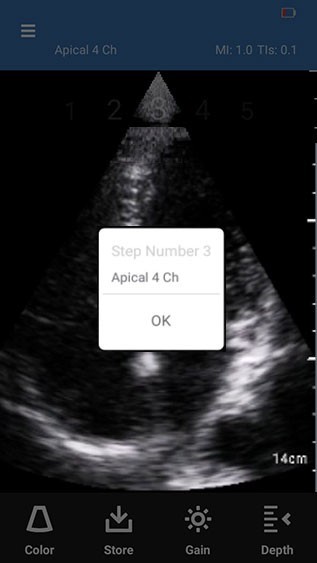

3. User Instructions message box displays for the step.

4. Press OK on the message box to navigate to the scan screen.

User instructions